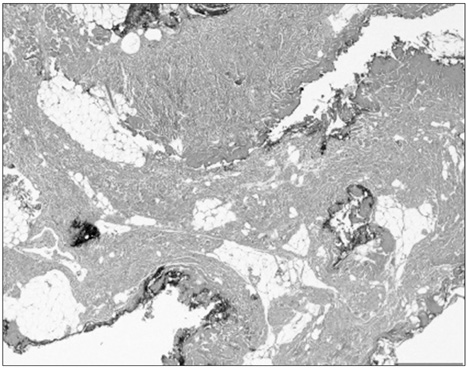

Fig. 1

Ultrasound finding of lesion (arrows).

Fig. 1 Ultrasound finding of lesion (arrows).